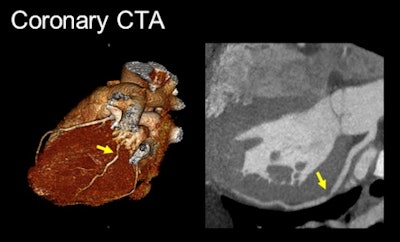

Images show concordant positive findings on stress CMR (above) and CTA (below) in a 42-year-old man with chest pain. The lateral wall stress-induced perfusion defect on CMR corresponds with the noncalcified severe stenosis involving a large obtuse marginal branch on coronary CTA. These CMR and CTA findings were confirmed on subsequent invasive angiography (bottom) with successful coronary stenting of the severe stenosis. All images courtesy of Dr. Marcus Chen.